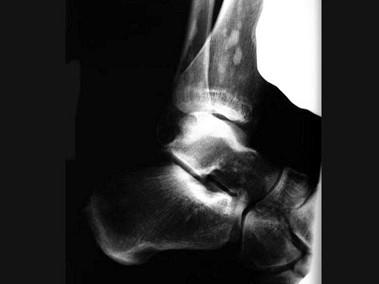

女,27岁,有外伤史,结合图像,最可能的诊断是?(?)A.骨斑点症B.骨梗死C.骨岛D.皮肤骨膜肥厚症E.石骨症

问题 女,27岁,有外伤史,结合图像,最可能的诊断是?(?)

选项 A.骨斑点症 B.骨梗死 C.骨岛 D.皮肤骨膜肥厚症 E.石骨症

答案 A